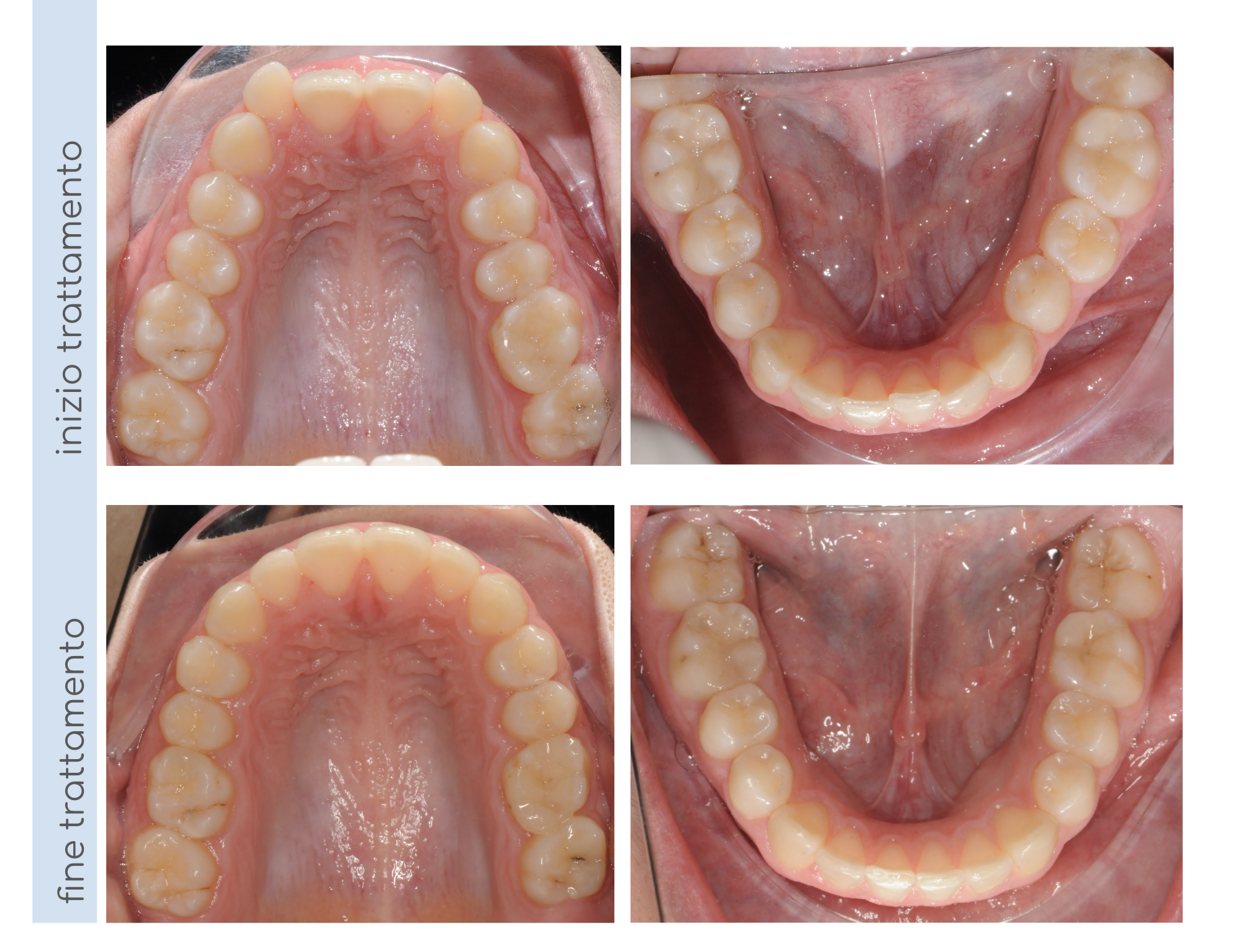

In questo caso, il paziente presentava un morso crociato posteriore a sinistra, intercettato precocemente e corretto in dentatura mista. Al termine della terapia intercettiva, una volta erotti tutti i denti permanenti, il nostro piccolo paziente ha iniziato una seconda fase di terapia con allineatori trasparenti per finalizzare il trattamento e allineare correttamente le arcate!

La paziente presentava una Il classe Il divisione con morso profondo, morso crociato posteriore a sinistra e deviazione delle linee mediane dentali. E stata trattata con apparecchio fisso ad entrambe le arcate per 18 mesi; al termine del trattamento abbiamo ottenuto una l classe bilaterale, l'apertura del morso, la correzione del morso crociato posteriore e un allineamento delle linee mediane dentali.